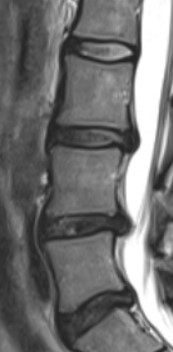

허리디스크는 MRI, CT, 근전도 검사를 통하여 진단할 수 있습니다.

허리디스크는 요추 추간판 탈출증으로

요추사이에 존재하는 추간판이 외부의 충격이나 퇴행성질환에 의하여 튀어나와

척수나 신경을 압박하여 허리통증, 저림, 근력약화, 운동제한 등을 일으키는 질병입니다.